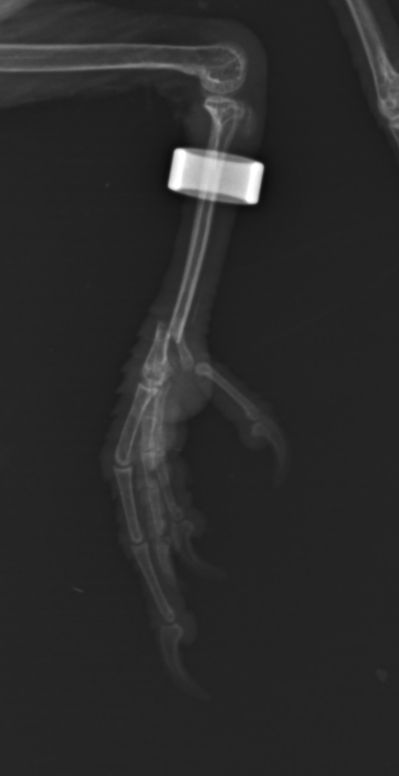

Bonsoir,

Une petite nouvelle, mais il faut bien regarder la photo.

178.jpg

178.jpg (10.42 Kio) Vu 27372 fois

Pas très visible mais je crois que pour lui, la saison de ski est foutue.

Heureusement, j'ai été très bien accueilli à l'ENV de Toulouse.

Donc en cage hôpital, avec un 'plâtre' pour 3 semaines.

Pour l'instant, le petit Touraco semble OK.

Après une petite visite à l'ENV, quelques nouvelles.

D'abord les faits !

181.jpg

181.jpg (7.79 Kio) Vu 26605 fois

Il semblerait qu'on voit que ça va mieux. Aussi, le petit 'plâtre' a sauté mais il reste en cage pour éviter de trop bouger.

Des nouvelles de notre petite histoire avec la dernière visite à l'ENV.

183.jpg

183.jpg (9.66 Kio) Vu 26104 fois

Le cal osseux semble bien formé, il a donc rejoint sa volière, fini les restrictions.